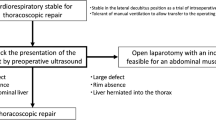

Three-dimensional model development

Two models, with identical diaphragmatic defects, were designed and built to simulate the operative steps of CDH repair via laparotomy and thoracoscopy with assessment of interobserver reliability of measuring the defect. Parental informed consent was obtained to use a pre-existing MRI scan from a foetus with a prenatal diagnosis of CDH for the purposes of designing a surgical simulation model. Stereolithography (STL) files were created from the patient MRI using the open-source software ITK-SNAP (v.3.8.0, www.itksnap.org). The size and relative proportions of the thorax, diaphragm and defect were delineated and segmented. The computer-assisted design (CAD) software Blender 3D (Blender Foundation, USA) and Fusion 360 (Autodesk Inc, USA) were used to clean, refine, and modify the ribcage, spine and pelvis.

For the thoracoscopic repair model, the left hemithorax was isolated and orientated in a right lateral position to simulate access to the left hemi-diaphragm. The ribs were reinforced at the vertebral bodies and costochondral joints with geometric shapes, and the scapula applied to the posterior ribcage. Geometric shapes were also added to the sternal side of the ribcage to allow fixation to the model base. For the model simulating repair via laparotomy, the entire rib cage was isolated and combined with the spine and pelvis as one component. This component was reinforced with geometric shapes to add strength and allow fixation to the base, simulating a baby lying supine.

Using measurements derived from the foetal MRI, moulds for silicone casting of soft organs and tissues were 3D-printed, including diaphragm, lung, liver, spleen and bowel. Platinum-catalysed silicone (Smooth-On Inc., Pennsylvania, United States) of varying hardness, and dyed with pigment, was used to maximise realism. The silicone components were applied to the 3D-printed model (Fig. 1). The silicone diaphragm was constructed based on measurements from the patient MRI. These measurements were replicated in the CAD software to create a diaphragm measuring 42 mm by 75 mm (Fig. 2), therefore, each hemi-diaphragm measured 42 mm by 37.5 mm. The entire diaphragm was used in the model of repair via laparotomy and the left hemi-diaphragm was used in the thoracoscopic repair. The defect was measured on the MRI and was added to the silicone diaphragm after curing. This measured 15 mm by 15 mm.

These two models assess several steps in the CDH repair procedure. The model provides anatomical landmarks for planning access. The models simulate: incision or thoracoscopic port placement, navigation of the chest cavity with a camera, identification of the defect, reduction of its content, assessment of the defect size, direct primary closure or patch placement and wound closure. Additionally, the models can be reused with replacement of parts that are sutured or incised.